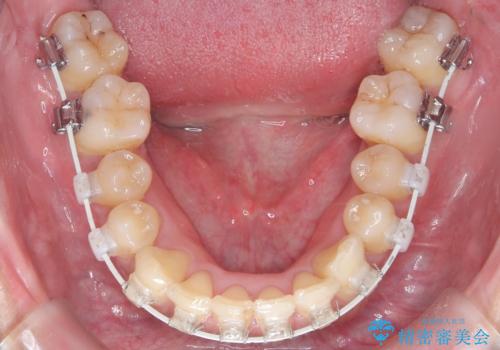

- 前歯のデコボコ(叢生)と、上下の歯の重なりが深い「ディープバイト(過蓋咬合)」を主訴にご来院されました。精密検査の結果、歯が並ぶスペースが不足しているため、上顎左右の小臼歯を抜歯することでスペースを確保し、全体の咬み合わせを改善する治療計画を立案しました。これにより、見た目の改善だけでなく、過度な咬み合わせによって生じる歯や顎への負担も軽減することを目指します。

今回の矯正治療では、まず歯が並ぶスペースを確保するため、上顎の小臼歯を抜歯しました。抜歯によってできたスペースを利用して前歯を奥へ移動させ、デコボコを解消。同時に、奥歯の咬み合わせを調整することで、深すぎた咬み合わせであるディープバイトも改善しました。治療の結果、長年気にされていた前歯のデコボコが解消され、理想的な歯並びに。さらに、正しい咬み合わせを獲得したことで、機能的にも安定した美しい口元になりました。